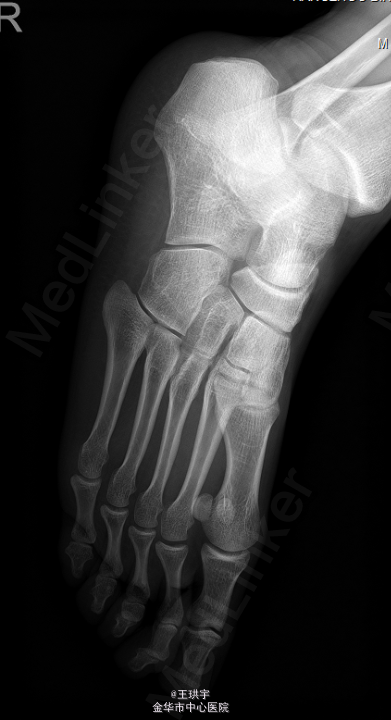

右足副舟骨畸形

后天性扁平足

患者,男,26岁,因“右足部外伤后疼7余年,加重6月 ”入院。

右踝及足背肿胀不明显,右足副舟骨可见明显红肿,皮温正常,足趾活动无殊,末梢循环感觉正常。余肢体无殊。外院 X片示副舟骨畸形.

初步诊断:右足副舟骨畸形,后天性扁平足.在全麻下行“右跟骨截骨内移+副舟骨切除+舟骨切复内固定术+石膏固定术”.